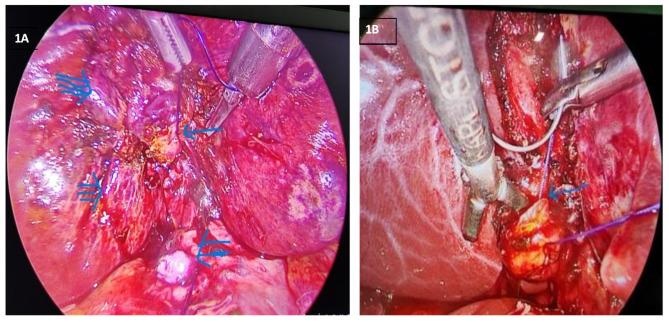

Subtotal laparoscopic cholecystectomy (LSC) is a rescue procedure in difficult case, retaining all advantages of minimally invasive surgery. The most reputed definition of subtotal cholecystectomy is the removal of 3/4th of gallbladder with closure of the infundibulum. The closure of the infundibulum can be with either intracorporeal interrupted suture or pre-knotted endo-loop. This study aims to share our experience with the stump closure techniques (either interrupted suture closure or endo-loop closure) during LSC so that the result of the study helps surgeons to choose an appropriate technique of the stump closure.

Nowadays, LSC is gaining preference over conversion to open procedure in difficult cholecystectomy cases. It is better to close the remnant stump of gallbladder with endo-loop to decrease biliary leak with addition advantage of shorter operative time, lesser intraoperative blood loss, shorter length of hospital stays and shorter duration of the drain placement. We recommend to close the remnant stump with endo-loop if the remnant stump is mobilized all around with intact and adequate length of all sides (including posterior one). However, the stump closure with interrupted suture should be opted if above mentioned criteria are not achieved.